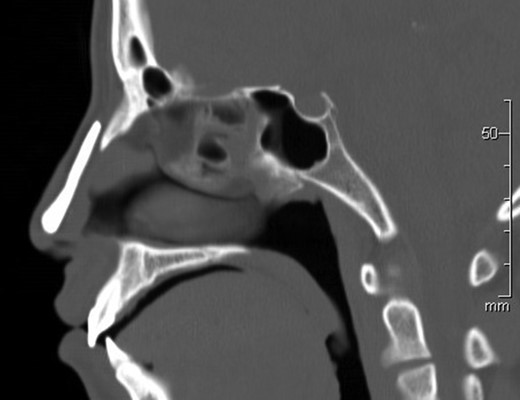

The patient was followed for 10 years after the third operation, and there were no complications, such as infection, malpositioning or exposure (Fig. 4). Computed tomography revealed no resorption or malpositioning of the implant (Fig. 5). A fourth operation (revisionary rhinoplasty) was performed to replace the hydroxyapatite prosthesis with an iliac bone graft at 16 years of age, after nasal development was completed.

Computed tomography revealed no resorption or malpositioning of the implant 10 years after implantation.